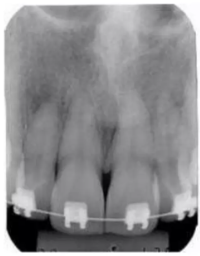

Diferentemente da radiografia panorâmica (figura 1), que traz uma visão geral de toda a região maxilar, a radiografia periapical (figura 2) abrange apenas uma determinada área, normalmente de 2 a 3 elementos dentários, da coroa ao final da raiz.

Fonte imagens: Material elaborado por Colégio Técnico São Bento. Disponível em: 20 radiologia-odontologica